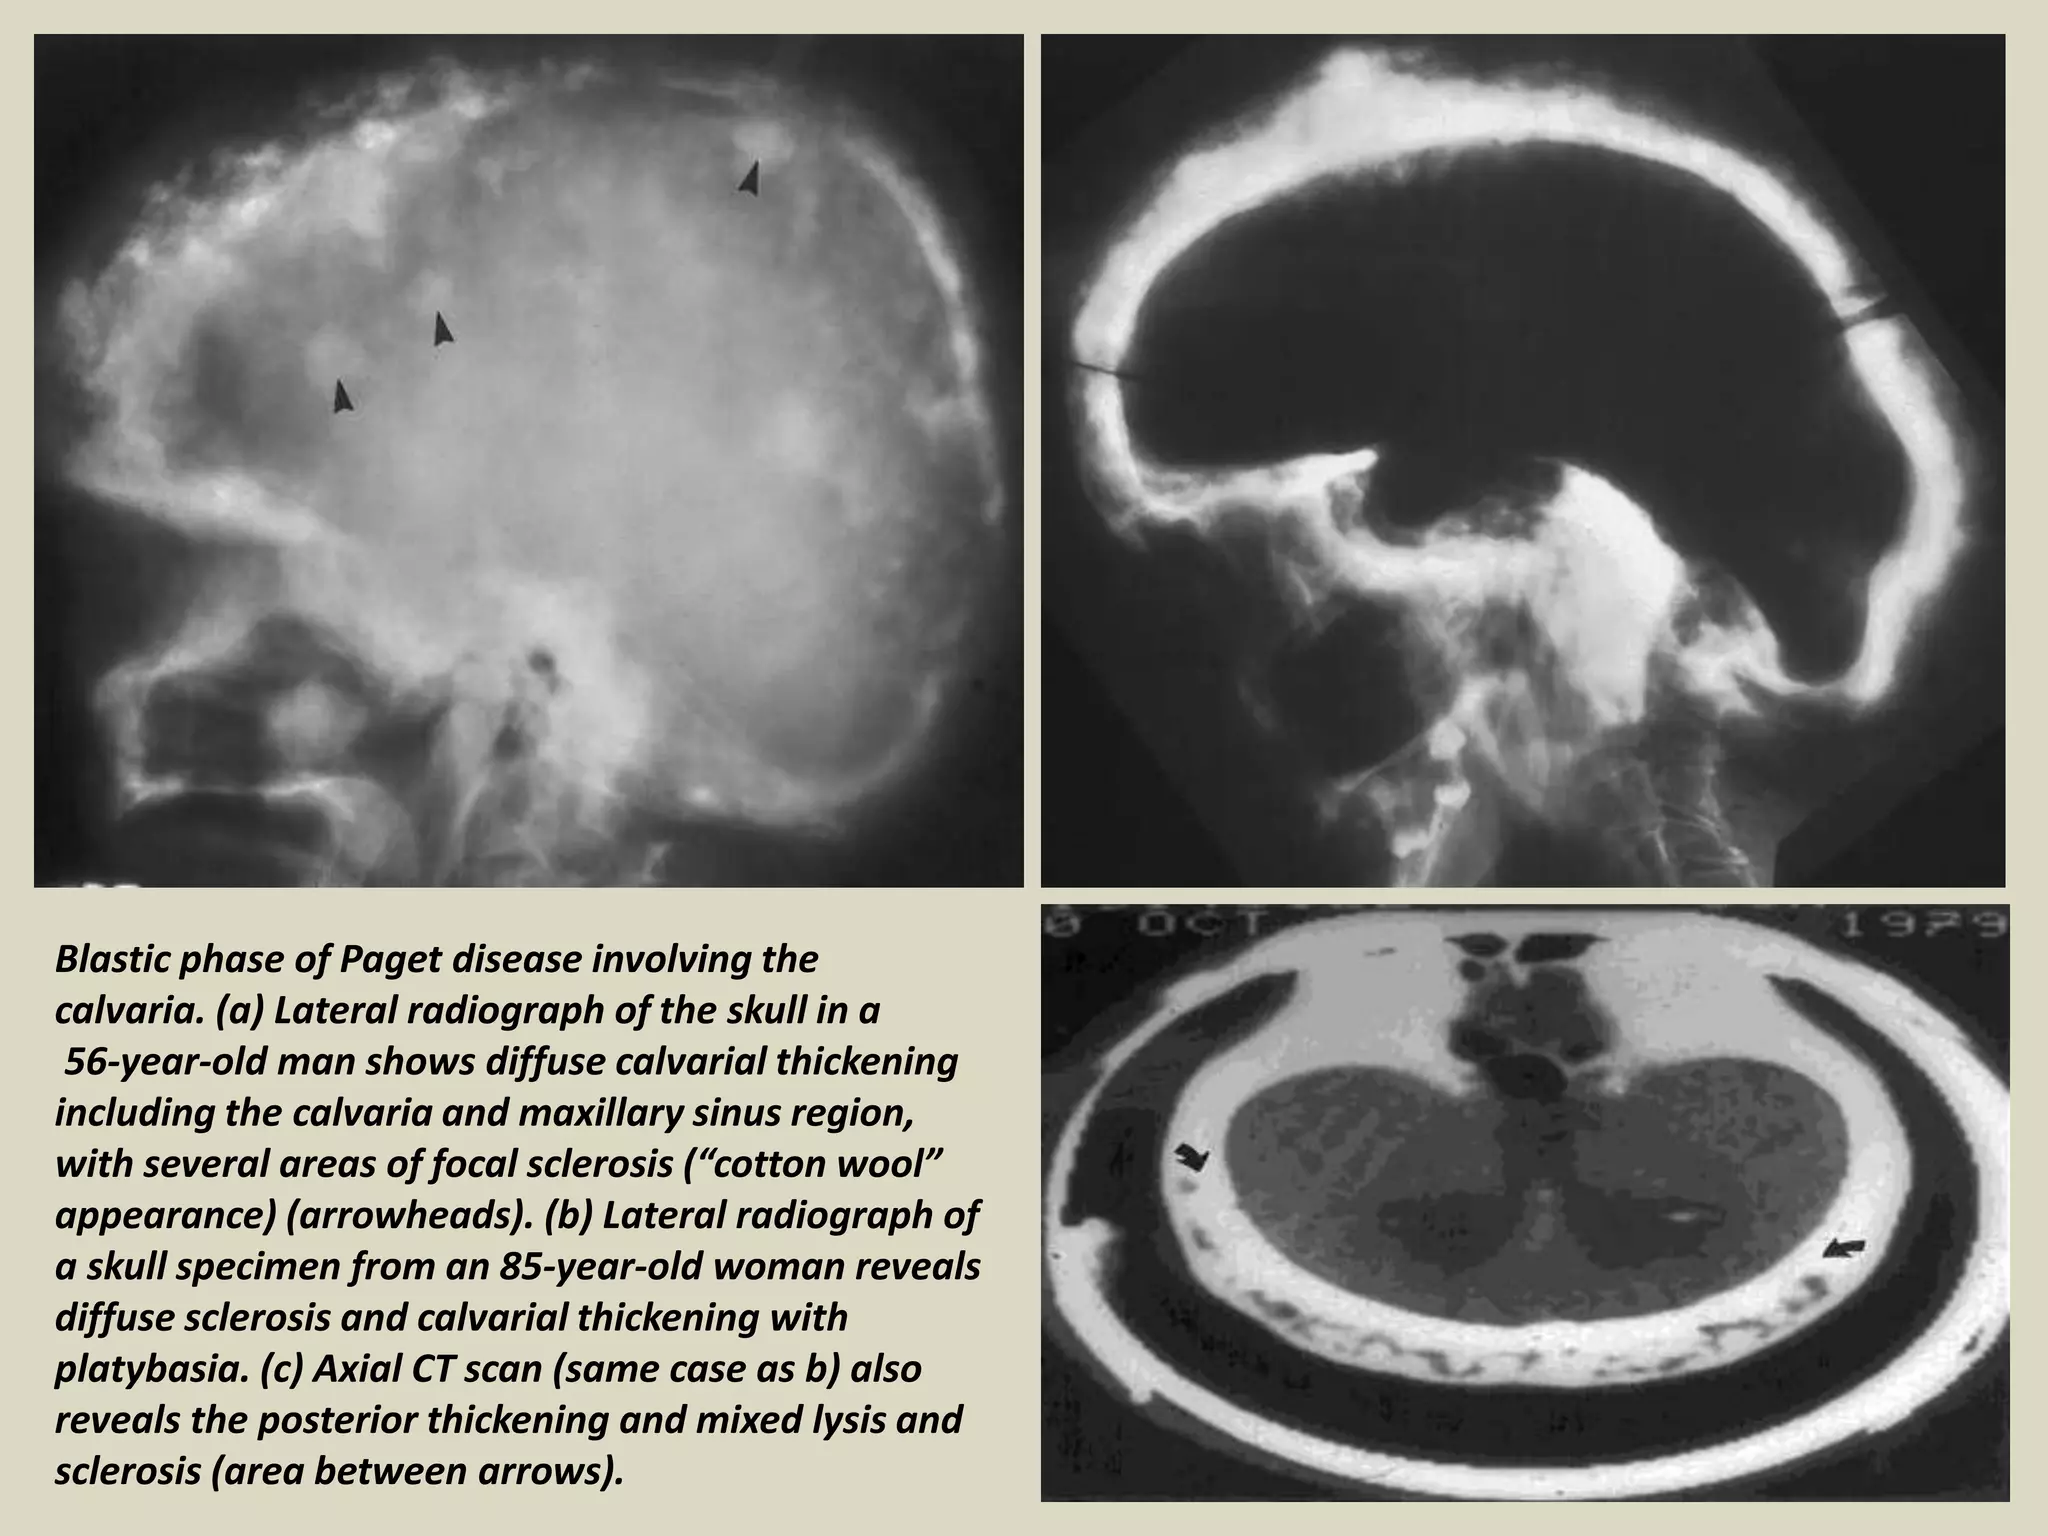

Blastic phase of Paget disease involving the

calvaria. (a) Lateral radiograph of the skull in a

56-year-old man shows diffuse calvarial thickening

including the calvaria and maxillary sinus region,

with several areas of focal sclerosis (“cotton wool”

appearance) (arrowheads). (b) Lateral radiograph of

a skull specimen from an 85-year-old woman reveals

diffuse sclerosis and calvarial thickening with

platybasia. (c) Axial CT scan (same case as b) also

reveals the posterior thickening and mixed lysis and

sclerosis (area between arrows).

Blastic phase ofPaget disease involving the calvaria. (a) Lateral radiograph of the skull in a 56-year-old man shows diffuse calvarial thickening including the calvaria and maxillary sinus region, with several areas of focal sclerosis (“cotton wool” appearance) (arrowheads). (b) Lateral radiograph of a skull specimen from an 85-year-old woman reveals diffuse sclerosis and calvarial thickening with platybasia. (c) Axial CT scan (same case as b) also reveals the posterior thickening and mixed lysis and sclerosis (area between arrows).